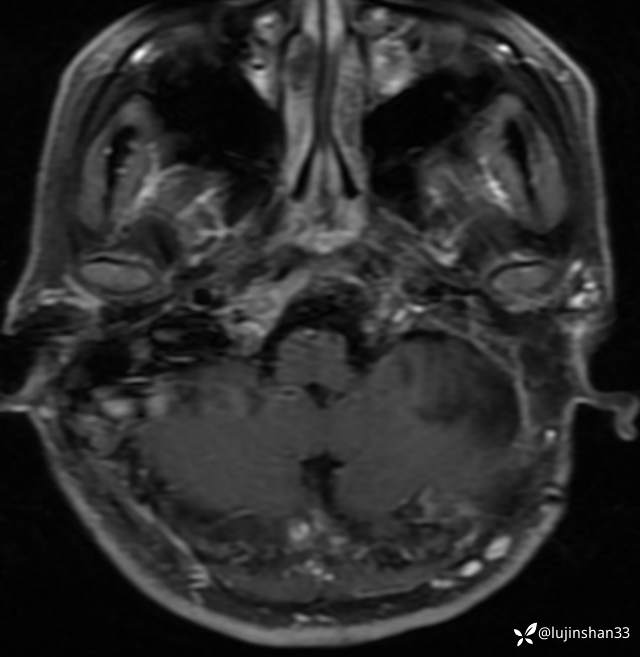

半年后复查

术后1年半复查CT及MRI